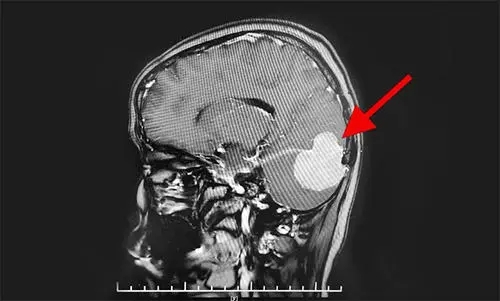

什么是小腦幕腦膜瘤?【西安高尚醫(yī)學(xué)影像】

小腦幕腦膜瘤(tentorialmeningionma)起源于小腦幕的任何一部分,可單純生長于幕上或幕下,也可幕上、幕下同時(shí)發(fā)生。臨床少見,小腦幕腦膜瘤占顱內(nèi)腦膜瘤的3%~5%。發(fā)病年齡40一50歲,女性明顯多于男性。臨床分型較多。分為幕上型、幕下型和啞鈴型。由于小腦幕在顱內(nèi)占據(jù)的范圍大,因此,小腦幕腦膜瘤的分類存在困難,Samii教授等人將小腦幕腦膜瘤分為六類:鞍旁(海綿竇)區(qū)腦膜瘤、小腦幕腦膜瘤、鐮幕腦膜瘤、巖斜區(qū)腦膜瘤、腦橋小腦角腦膜瘤和竇匯旁腦膜瘤。其中,單純的小腦幕腦膜瘤少見。

1.依靠CT掃描或MRI檢查。血管造影對(duì)檢查橫竇通暢情況有幫助。在影像診斷上應(yīng)該注意了解:①腫瘤向幕下還是幕上生長。②腫瘤與橫竇的關(guān)系。③小腦幕切跡前的腫瘤與腦干的關(guān)系。